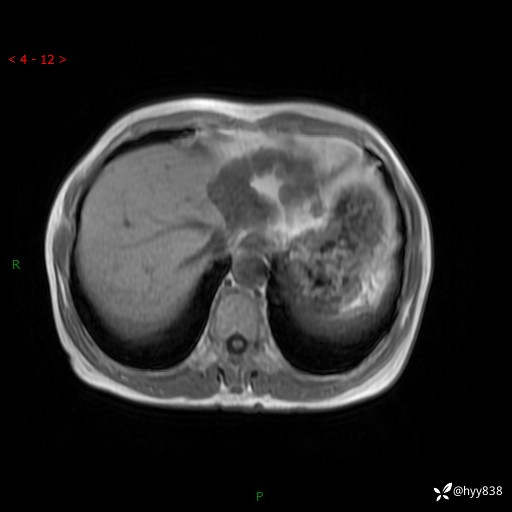

老年女性,偶然发现肝脏占位,综合各个序列,你考虑什么---结果公布

主诉:发现肝脏占位性病变2天

简要病史:患者2天前因“腰疼”至当地医院就诊时发现肝脏左叶占位性病变,无发热、畏寒,无皮肤黄染,无腹痛、腹泻,无恶心、呕吐、厌油等不适,今进一步诊治遂来我院就诊,门诊以“肝脏占位性病变性质待查”收入我科。 起病以来,患者精神、睡眠一般,饮食欠佳,二便正常,体力、体重无明显减轻,

临床诊断:肝占位

肝脏MRI平扫(同反相位)

T2WIfs+DWI

增强(动脉期+静脉期+延迟期)